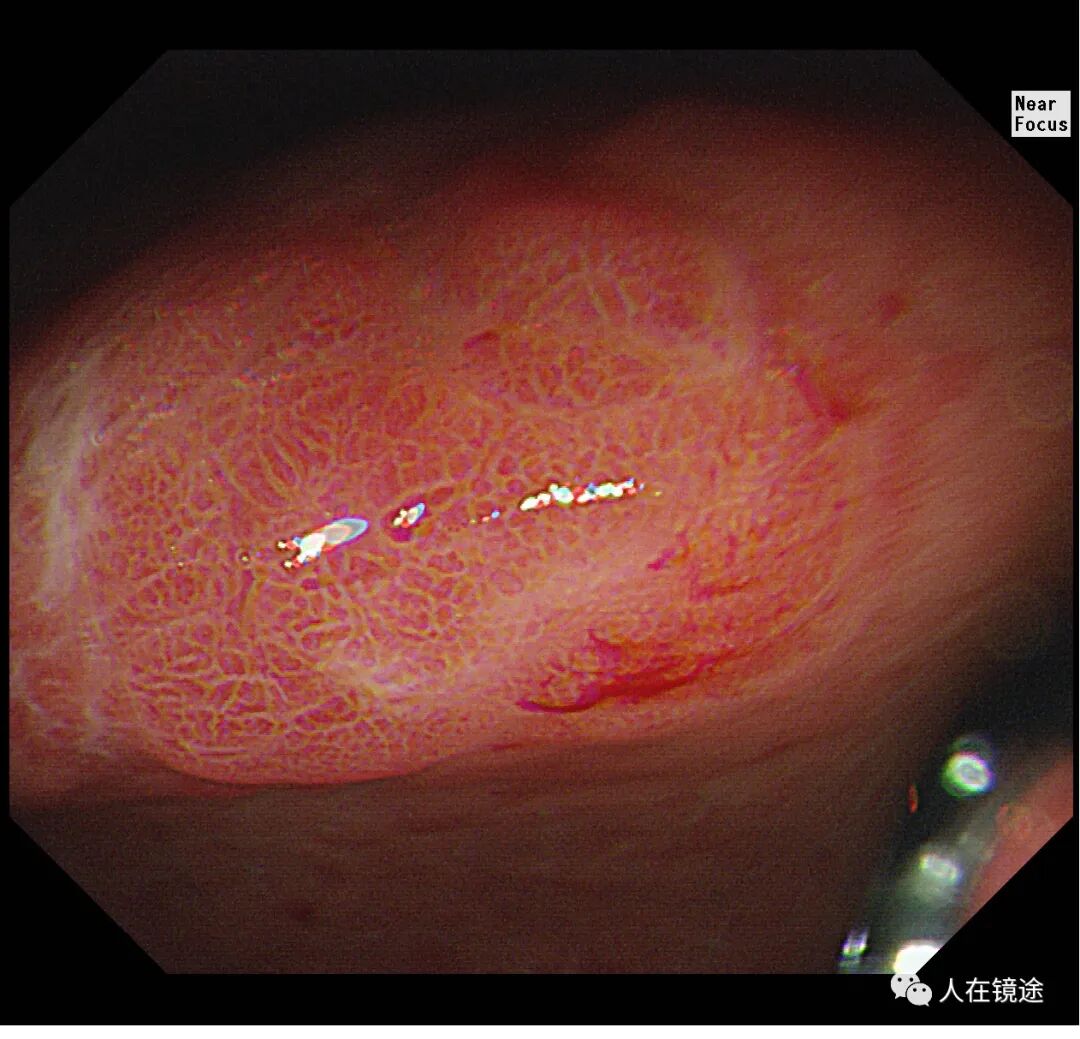

患者某某,女性,59岁,无症状胃镜检查示胃窦小弯见一0.8*1.2cmIIa粘膜发红病变,表面粗糙。

白光示胃窦粘膜红白相间,以白为主,胃窦小弯见一0.8*1.2cmIIa粘膜发红病变,表面粗糙。电子胃镜镜是什么奥林巴斯HQ290电子胃镜诊断胃窦早癌一例分享_https://www.jmylbn.com_新闻资讯_第3张

白光+近焦示:胃窦小弯见一0.8*1.2cmIIa粘膜发红病变,微结构稍紊乱,表面粘膜高低不平伴自发性出血。